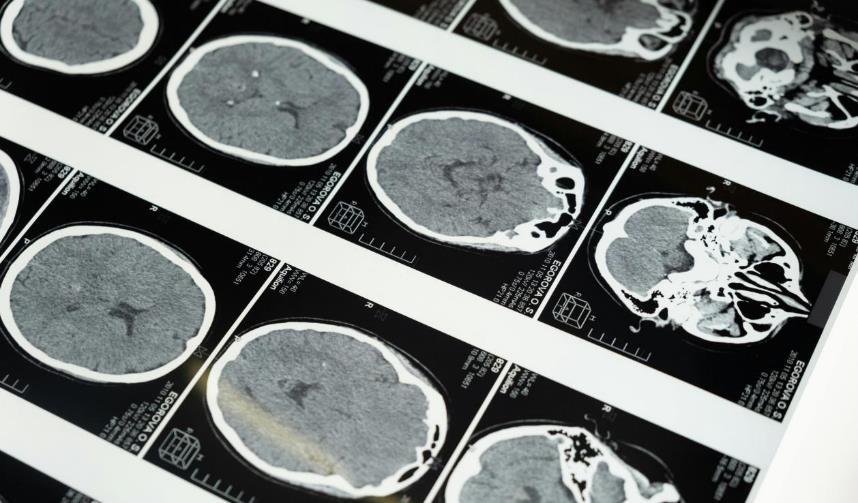

提到脑卒中,很多人会混淆 “出血性”和“缺血性”,简单来说,出血性和缺血性脑卒中的核心区别在于“破”与“堵”。出血性脑卒中属于脑血管破裂导致血液溢出,从而压迫脑组织,常引发剧烈头痛;而缺血性脑卒中则是因血栓导致血管闭塞,血流不通,脑组织因缺血缺氧而受损,通常表现为手脚无力或麻木。两者发病机理截然不同,一个是血管“漏了”,一个是血管“堵了”。但对占大多数的缺血性脑卒中来说,救治的核心逻辑只有一个:尽快溶解堵塞血管的血栓,恢复脑部供血。

很多人对溶栓治疗存在误解,认为溶栓治疗可能会增加颅内出血的风险,但这种风险的发生率极低,且医生会在治疗前进行严格评估,通过头颅 CT 等检查排除出血性脑卒中,同时评估患者的年龄、基础病、凝血功能等指标,权衡利弊后再决定是否进行治疗。相比之下,错过溶栓时间导致的终身残疾,对患者和家庭的影响更为深远。